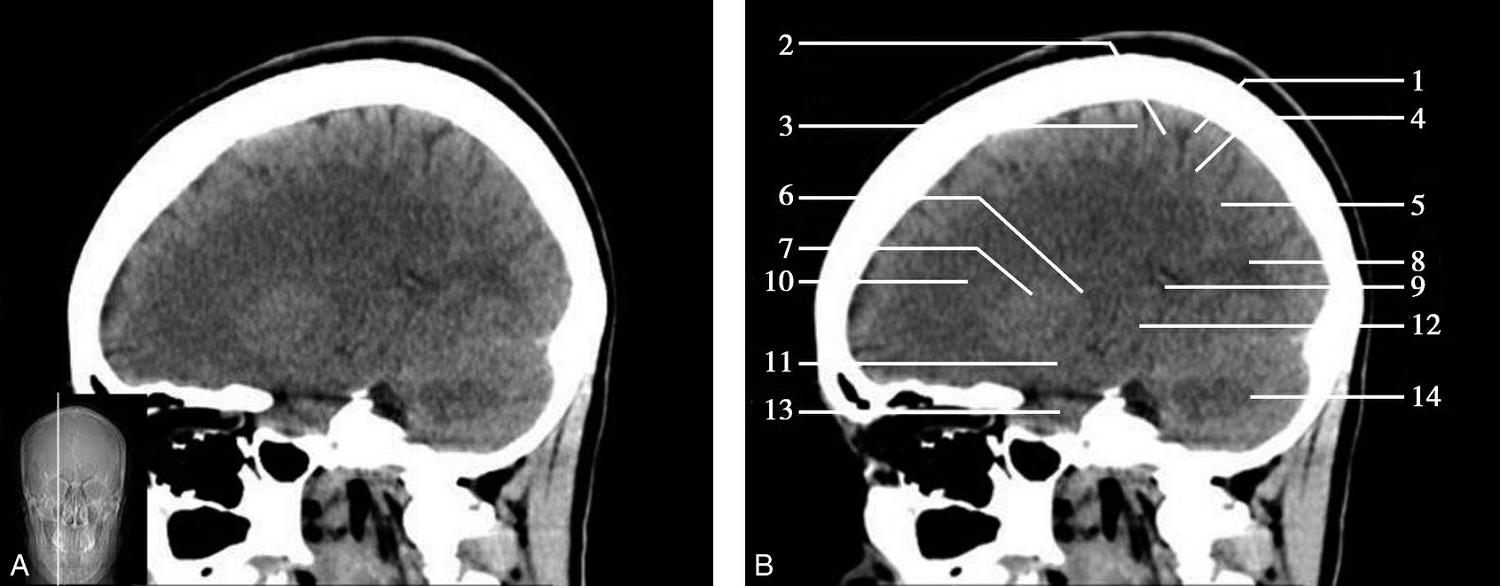

图1-2-59 正中矢状面CT

A.矢状面;B.矢状面标注

1.中央沟;2.扣带回;3.胼胝体体部;4.侧脑室;5.中脑;6.胼胝体膝部;7.穹隆;8.第三脑室;9.胼胝体压部;10.垂体;11.中脑导水管;12.第四脑室;13.脑桥;14.蝶窦;15.斜坡;16.小脑扁桃体;17.延髓

图1-2-60 正中矢状面骨窗CT

1.顶骨;2.枕骨;3.斜坡;4.额骨;5.蝶鞍

此层面可显示胼胝体全貌,它位于层面中央区域,是呈上凸下凹的弧形结构,由前向后分为嘴、膝、体和压四部分。扣带回环绕胼胝体上方,扣带沟位于扣带回的上方。大脑半球中部和后部分别可见较深且恒定的中央沟和顶枕沟。中央沟为是额叶顶叶分界标志。

胼胝体下方为侧脑室及穹窿,第三脑室借穹窿与前上方的侧脑室体部分开,背侧丘脑的内侧面以及中脑顶盖分别为第三脑室的外侧壁和底。第三脑室向前籍室间孔与侧脑室相通,向下经中脑导水管通第四脑室。中脑腔狭窄呈管状,即称为中脑导水管,中脑导水管畸形,常见者为导水管的分叉畸形和狭窄,其次可见中脑导水管膈膜,造成先天性脑积水。

脑干由中脑、脑桥和延髓组成,自第三脑室底向下后稍斜行,移行于颈髓。由上至下,脑干腹侧可见脚间池、桥前池和延髓池,脑干背侧可见大脑大静脉池、四叠体池和小脑延髓池。

垂体位于蝶鞍内,其前部为腺垂体,后上部分为神经垂体。垂体下方为鞍底及蝶窦,上缘因鞍膈存在而平直,垂体借垂体柄向上连于丘脑下部。垂体的前上方见视交叉和视束。斜坡作为前颅窝底的重要组成部分与多个重要结构相比邻,矢状位呈三角形,颅内肿瘤或颅外鼻咽部恶性肿瘤均可侵犯至此,原发肿瘤常见为脊索瘤。小脑幕居枕叶和小脑之间,向后下连接窦汇,向前至中脑后方游离,称小脑幕切迹。小脑幕下方为小脑扁桃体。成年人小脑扁桃体下缘由枕骨大孔向下疝入椎管超过5mm称为Chiari畸形,以矢状位显示最佳。